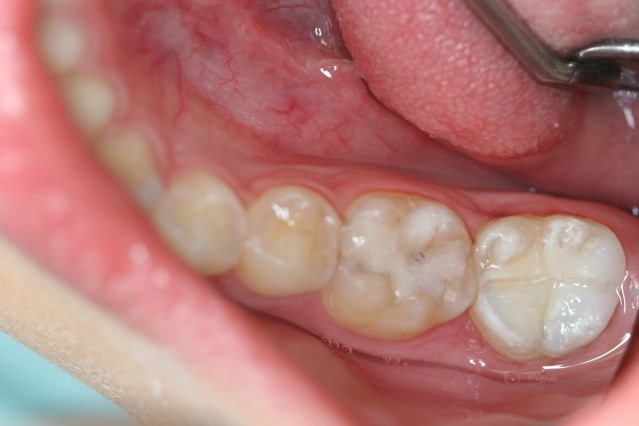

Streszczenie: W przypadku zębów stałych niedojrzałych, zgodnie z wytycznymi American Academy of Pediatric Dentistry (AAPD), możemy zastosować metodę prowadzącą do apeksogenezy, apeksyfikacji lub metodę rewaskularyzacji. Najbardziej korzystna jest metoda, która prowadzi do zachowania zęba z żywą miazgą. W pracy przedstawiono procedurę apeksyfikacji z zastosowaniem materiału Mineral Trioxide Aggregate (MTA) w zębie trzonowym 47 u pacjenta w wieku rozwojowym. Apeksyfikacja to proces stymulowanego formowania wierzchołka korzenia za pomocą preparatów o działaniu odontotropowym pod nieobecność żywej miazgi w kanale.